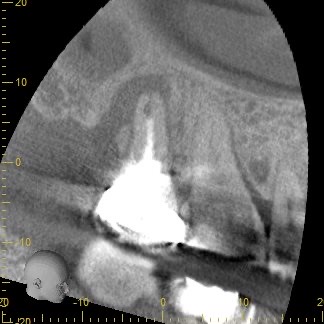

3ヶ月経過後のCT画像です。

術前のCT画像と比較すると、歯根周囲の黒くなっていた部分の骨の回復を認めました😊

ここまで回復すれば長期的な安定期が期待できるため、被せ物を作製していきます。